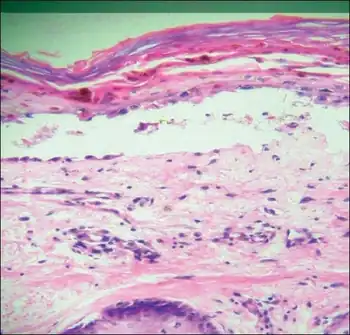

| Transfusion associated graft versus host disease -Mononuclear cell infiltration and inflammation of affected epithelium, with focal vacuolation of basal epithelial cells | |

TA-GvHD can be suspected from a biopsy of the affected skin or liver,[3] and established by HLA analysis of the circulating lymphocytes. This testing can identify circulating lymphocytes with a different HLA type than the tissue cells of the host.